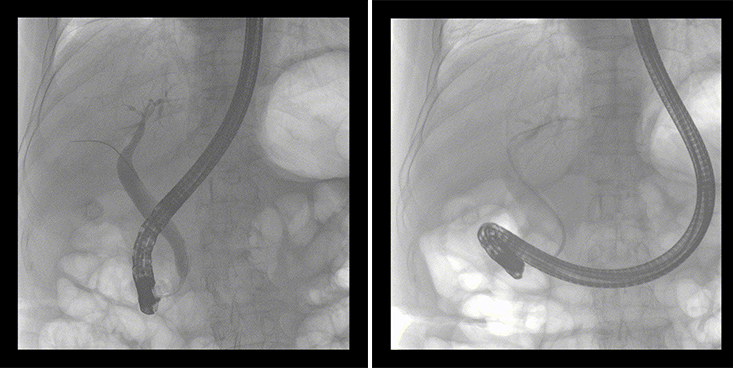

一位86歲的女性患者近來出現(xiàn)腹痛,入院后CT檢查并結(jié)合臨床表現(xiàn)被診斷為急性膽囊炎伴膽囊結(jié)石。經(jīng)專家團(tuán)隊協(xié)商并與患者家屬溝通,決定對患者實施經(jīng)內(nèi)窺鏡逆行胰膽管造影(ERCP)。

ERCP(經(jīng)十二指腸鏡下逆行胰膽管造影)現(xiàn)已成為比較成熟的微創(chuàng)介入技術(shù),被廣泛的應(yīng)用于臨床,ERCP也是消化內(nèi)鏡領(lǐng)域難度大、風(fēng)險大、技術(shù)復(fù)雜的微創(chuàng)手術(shù),其并發(fā)癥多為致命性,ERCP手術(shù)對醫(yī)生的要求很高,因此,ERCP醫(yī)生又被稱為“刀尖上的舞者”。因為手術(shù)難度較大,過程復(fù)雜,需要C形臂精準(zhǔn)的配合,對影像清晰度的要求也非常高。

普愛醫(yī)療移動式平板中C為本次ERCP手術(shù)提供實時無損高清影像,幫助醫(yī)生精準(zhǔn)定位?!俺上裥Ч浅0?!完全不輸國際大牌的醫(yī)學(xué)影像設(shè)備……”鼓樓醫(yī)院江北國際醫(yī)院內(nèi)鏡中心手術(shù)團(tuán)隊對普愛醫(yī)療移動式平板中C的成像效果給與了高度的評價。

在消化內(nèi)科主任的領(lǐng)導(dǎo)和多科室全力配合下,南京鼓樓醫(yī)院江北國際醫(yī)院成功完成了首例ERCP手術(shù)。